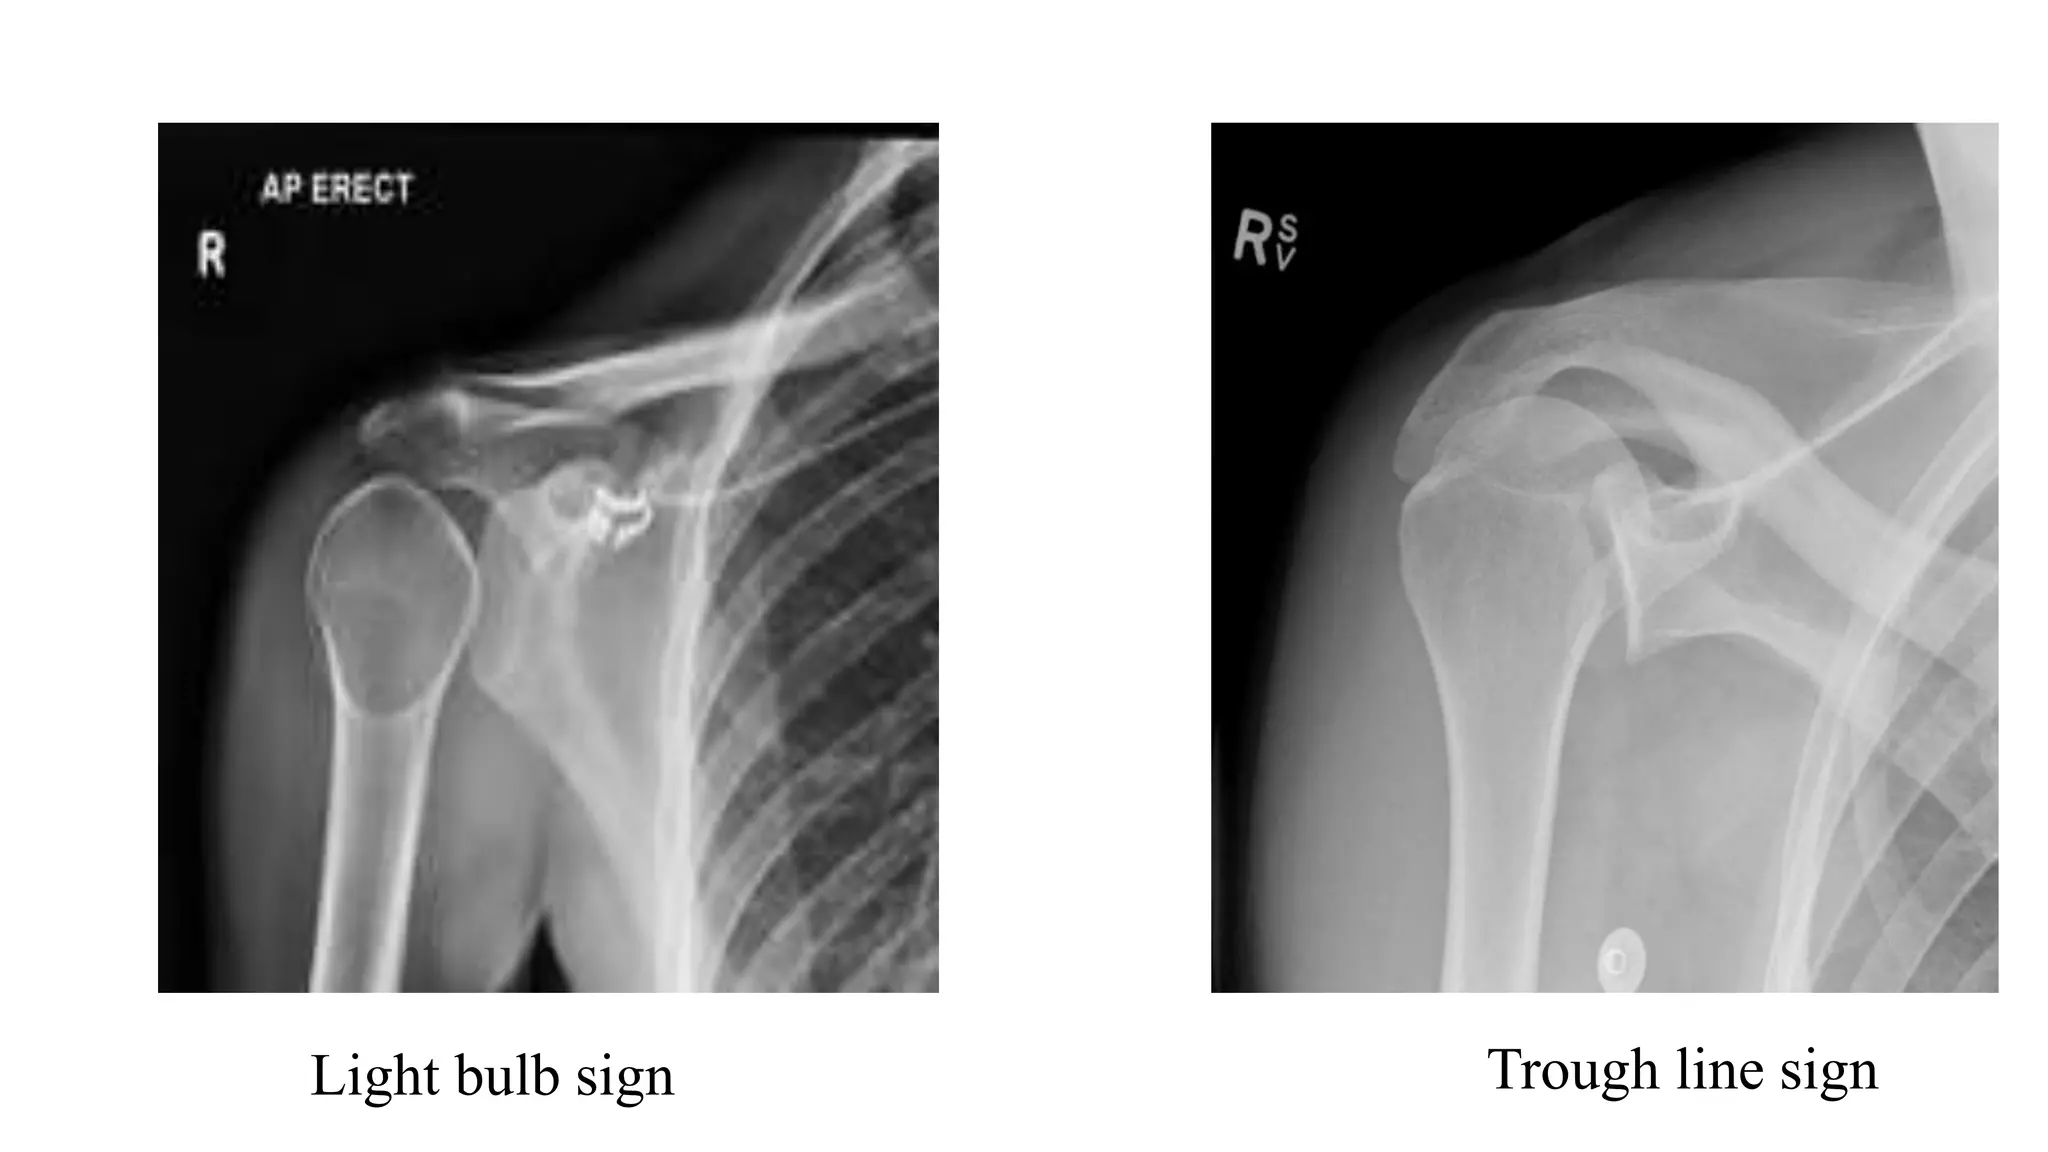

Posterior Shoulder Dislocation

• Radiological signs on AP view:

• Internal rotation of the humerus

• Light bulb sign

• The ‘rim sign’ – Widening of the glenohumeral space

• Trough line sign - the anterior aspect of the humeral head becomes

impacted against the posterior glenoid rim

Light bulb sign Trough line sign